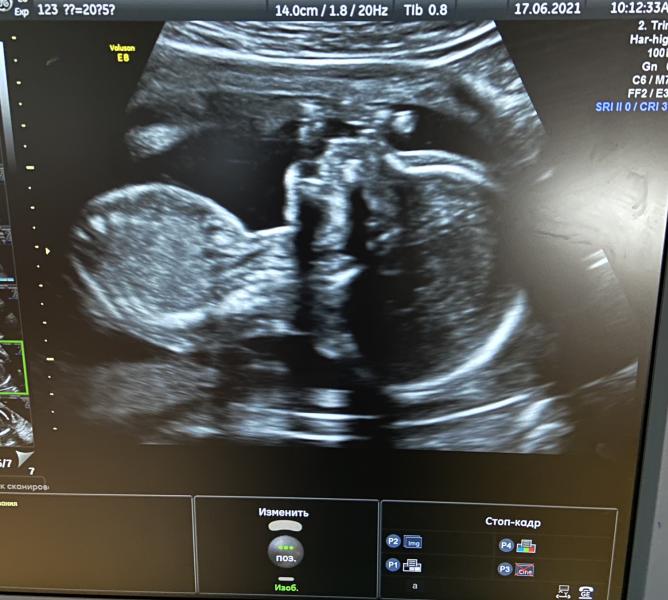

Ходила на 2е Узи, в РД18 .

Повидались с малышом, правда он все прятал лицо. В итоге в 2 захода и моими танцами на кушетке, соизволил лицо показать! Все хорошо идёт, чему я очень рада! На фоточке ручка у лица все же )

А вы сегодня же были на УЗИ😍Я сегодня тоже была там УЗИ 20 нед😁